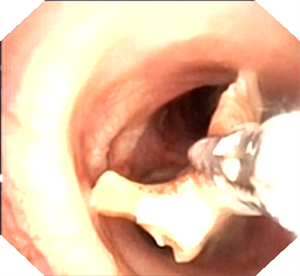

一位外地老年男性患者,因 “肺炎” 一直咳嗽、气喘不愈,活动量差。在当地医院多次住院治疗,症状仍无明显改善。后因 “液气胸” 急诊入我院,呼吸科医生仔细阅片后发现,患者右中间段支气管内有一类圆形 “新生物” 阻塞管腔。收住院后,呼吸内镜团队为患者进行全麻支气管检查,清晰见到右中间段支气管内一黄豆异物阻塞。由于异物 “圆滑”,直接取出困难,医生巧妙地用圈套器 “捆扎” 住黄豆,顺利完整拉出,患者快速康复出院。